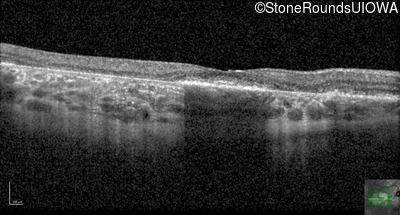

AR Stargardt Disease (IIA)

Age at visit: 61 years

This 61 year old woman first noticed an abnormality in the center of her vision in dim light when she was 8 years old.

Diagnosis & molecular findings

Disease Gene Allele 1 variant(s) Allele 2 variant(s) Inheritance mode

AR Stargardt Disease ABCA4 Pro1380Leu CCG>CTG IVS40+5 G>A AR